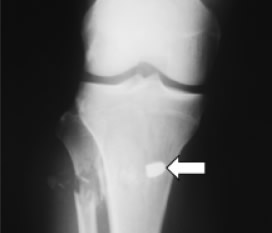

Masculino de 36 años, previamente sano, ocupación policía. Ingresó posterior a herida por proyectil de arma de fuego en pierna izquierda que condicionó fractura de peroné (Figura 1). Presentó crisis convulsivas tónico-clónicas generalizadas, estado confusional, dificultad respiratoria e hipoxemia, por lo que se ingresó a la UTI. A la exploración física con FC de 130/m, FR de 35/m, PA de 100/60, SatO2 al aire ambiente al 70%, Temperatura de 38 ºC. Con estertores crepitantes e hipoaereación bibasal de predominio izquierdo. Presencia de petequias a nivel conjuntival (Figura 2). En la citometría hemática con trombocitopenia de 150,000/mm3. En la Rx de tórax con infiltrado intersticial bibasal de predominio izquierdo (Figura 3). En la angiotomografía computada de tórax se observó infiltrado intersticial y áreas de condensación de predominio basal y no se observaron coágulos en el sistema arterial pulmonar. La resonancia magnética cerebral con imágenes hiperintensas corticales bilaterales (Figura 4).

Figura 1. Fractura multifragmentaria del tercio superior de peroné.

Nótese la trayectoria del proyectil de arma de fuego (flecha).